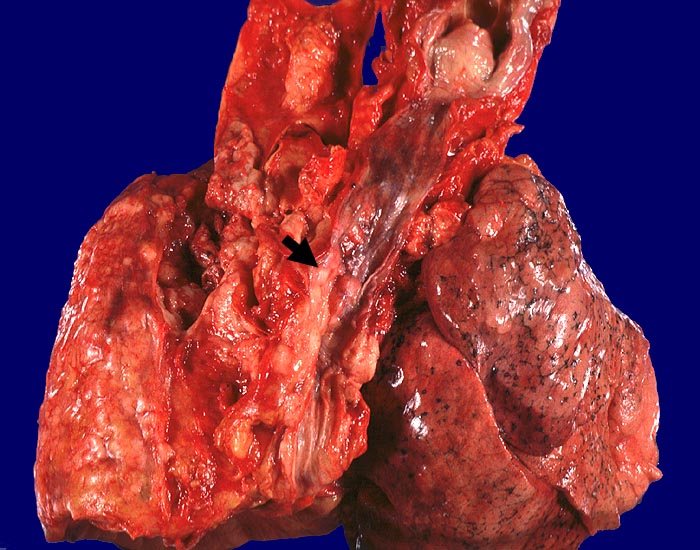

Kleinzellige Karzinome entwickeln sich bevorzugt zentral.

• Drei Bronchialschleimhautbiopsien ausgekleidet von respiratorischem Flimmerepithel.

• Blauer, sehr zelldichter solider Tumor in der Submukosa des mittleren Biopsiefragmentes. Die beiden anderen Schleimhautfragmente sind tumorfrei.